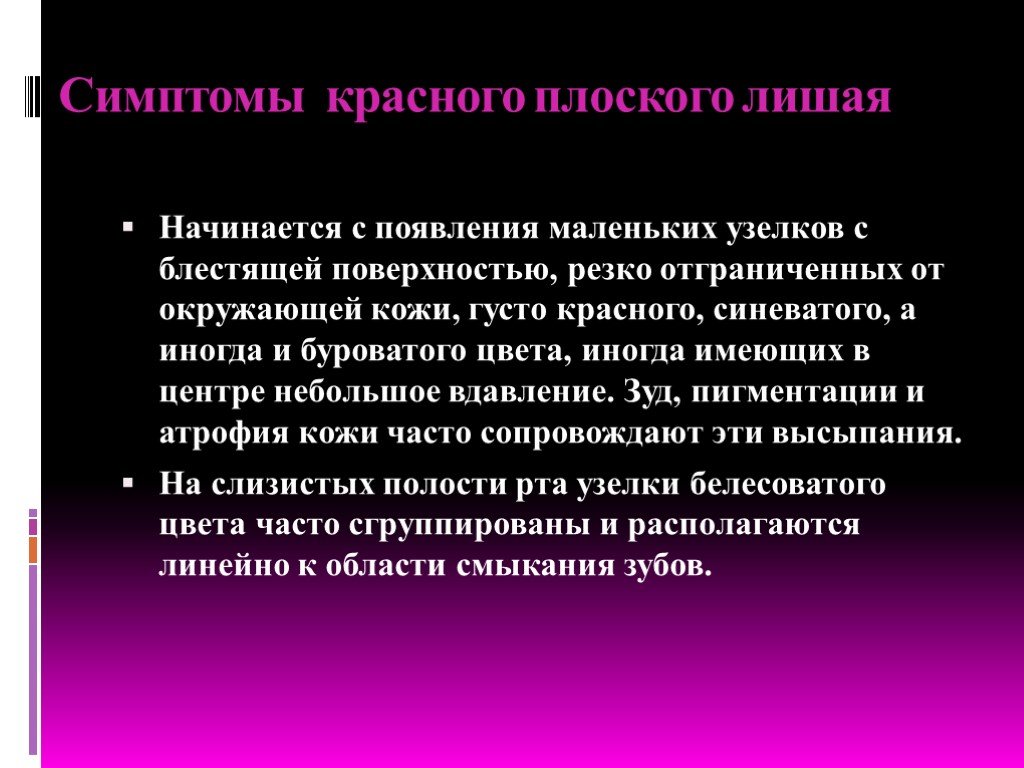

Фото Красного Плоского

Фото Красного Плоского 103 фото